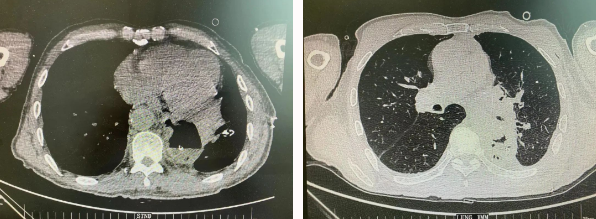

近日,胸科醫(yī)院執(zhí)行院長李小飛教授帶領(lǐng)胸外科一病區(qū)團(tuán)隊(duì)完成一臺(tái)復(fù)雜胸外科手術(shù):食管癌與肺癌同期手術(shù)。

患者王某不幸同時(shí)患食管癌與左肺癌,病理類型系雙源發(fā)腫瘤,食管為鱗癌、肺為腺癌。食管癌和肺癌為胸外科最常見的疾病,但同時(shí)患兩種疾病,十分罕見。家屬輾轉(zhuǎn)多個(gè)醫(yī)院,得知李小飛院長擅長胸外科復(fù)雜手術(shù),慕名來西安國際醫(yī)學(xué)中心醫(yī)院。

經(jīng)過李小飛教授、李文海副教授、穆強(qiáng)副主任醫(yī)師團(tuán)隊(duì)積極準(zhǔn)備,排除手術(shù)禁忌;經(jīng)過全科術(shù)前充分討論,大家認(rèn)為:如果分兩次進(jìn)行手術(shù),另一種疾病勢必會(huì)受到影響,腫瘤可能進(jìn)展。胸外科手術(shù)對(duì)呼吸循環(huán)影響較大,同期實(shí)施兩個(gè)手術(shù)更要小心謹(jǐn)慎。李小飛教授主持術(shù)前討論,設(shè)計(jì)合理手術(shù)方式,由于食管癌胸腔鏡手術(shù)為右側(cè)入路,但為兼顧左肺癌手術(shù),則采用傳統(tǒng)左開胸手術(shù)。

2022年4月25日,由李小飛教授主刀,同期行左側(cè)開胸:食管癌根治術(shù) 左肺癌根治術(shù),一次手術(shù)同時(shí)根治兩種惡性腫瘤疾病。經(jīng)過精細(xì)手術(shù)及術(shù)后管理,患者術(shù)后十天,恢復(fù)良好,進(jìn)食良好,現(xiàn)已出院。